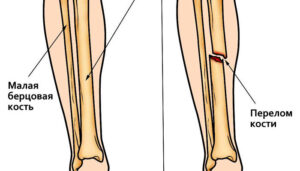

Перелом шеи

Перелом шейки матки — серьезная травма. Если не лечить должным образом, существует высокий риск полного или частичного паралича и возможность смерти. Человек становится инвалидом, даже если не травмируется спинной мозг. Пациенту следует немедленно обратиться за помощью к врачу, чтобы скрытые воспалительные процессы не остались незамеченными. Перелом шеи: причины Есть несколько важных причин, которые приводят к …